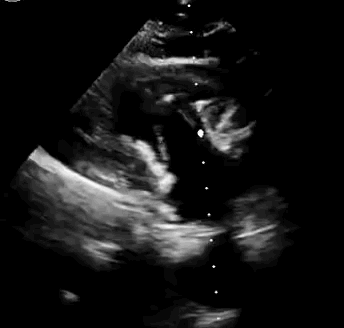

本次臨床前研究經(jīng)右側(cè)頸靜脈置入LuX-Valve Plus輸送系統(tǒng)可調(diào)彎鞘管,在DSA及超聲引導(dǎo)下將人工三尖瓣瓣膜植入到原有三尖瓣位置,利用獨特的錨定技術(shù)將人工瓣膜支架可靠固定在預(yù)定的位置。

上海中山醫(yī)院葛均波院士、錢菊英院長、周達新教授、潘文志教授、潘翠珍教授、李偉教授共同完成此次臨床前研究。術(shù)后葛均波院士對Lux-Valve Plus的器械操作性能給予了高度評價,DSA和超聲影像也顯示出在本次研究中Lux-Valve Plus的安全性和有效性俱佳。